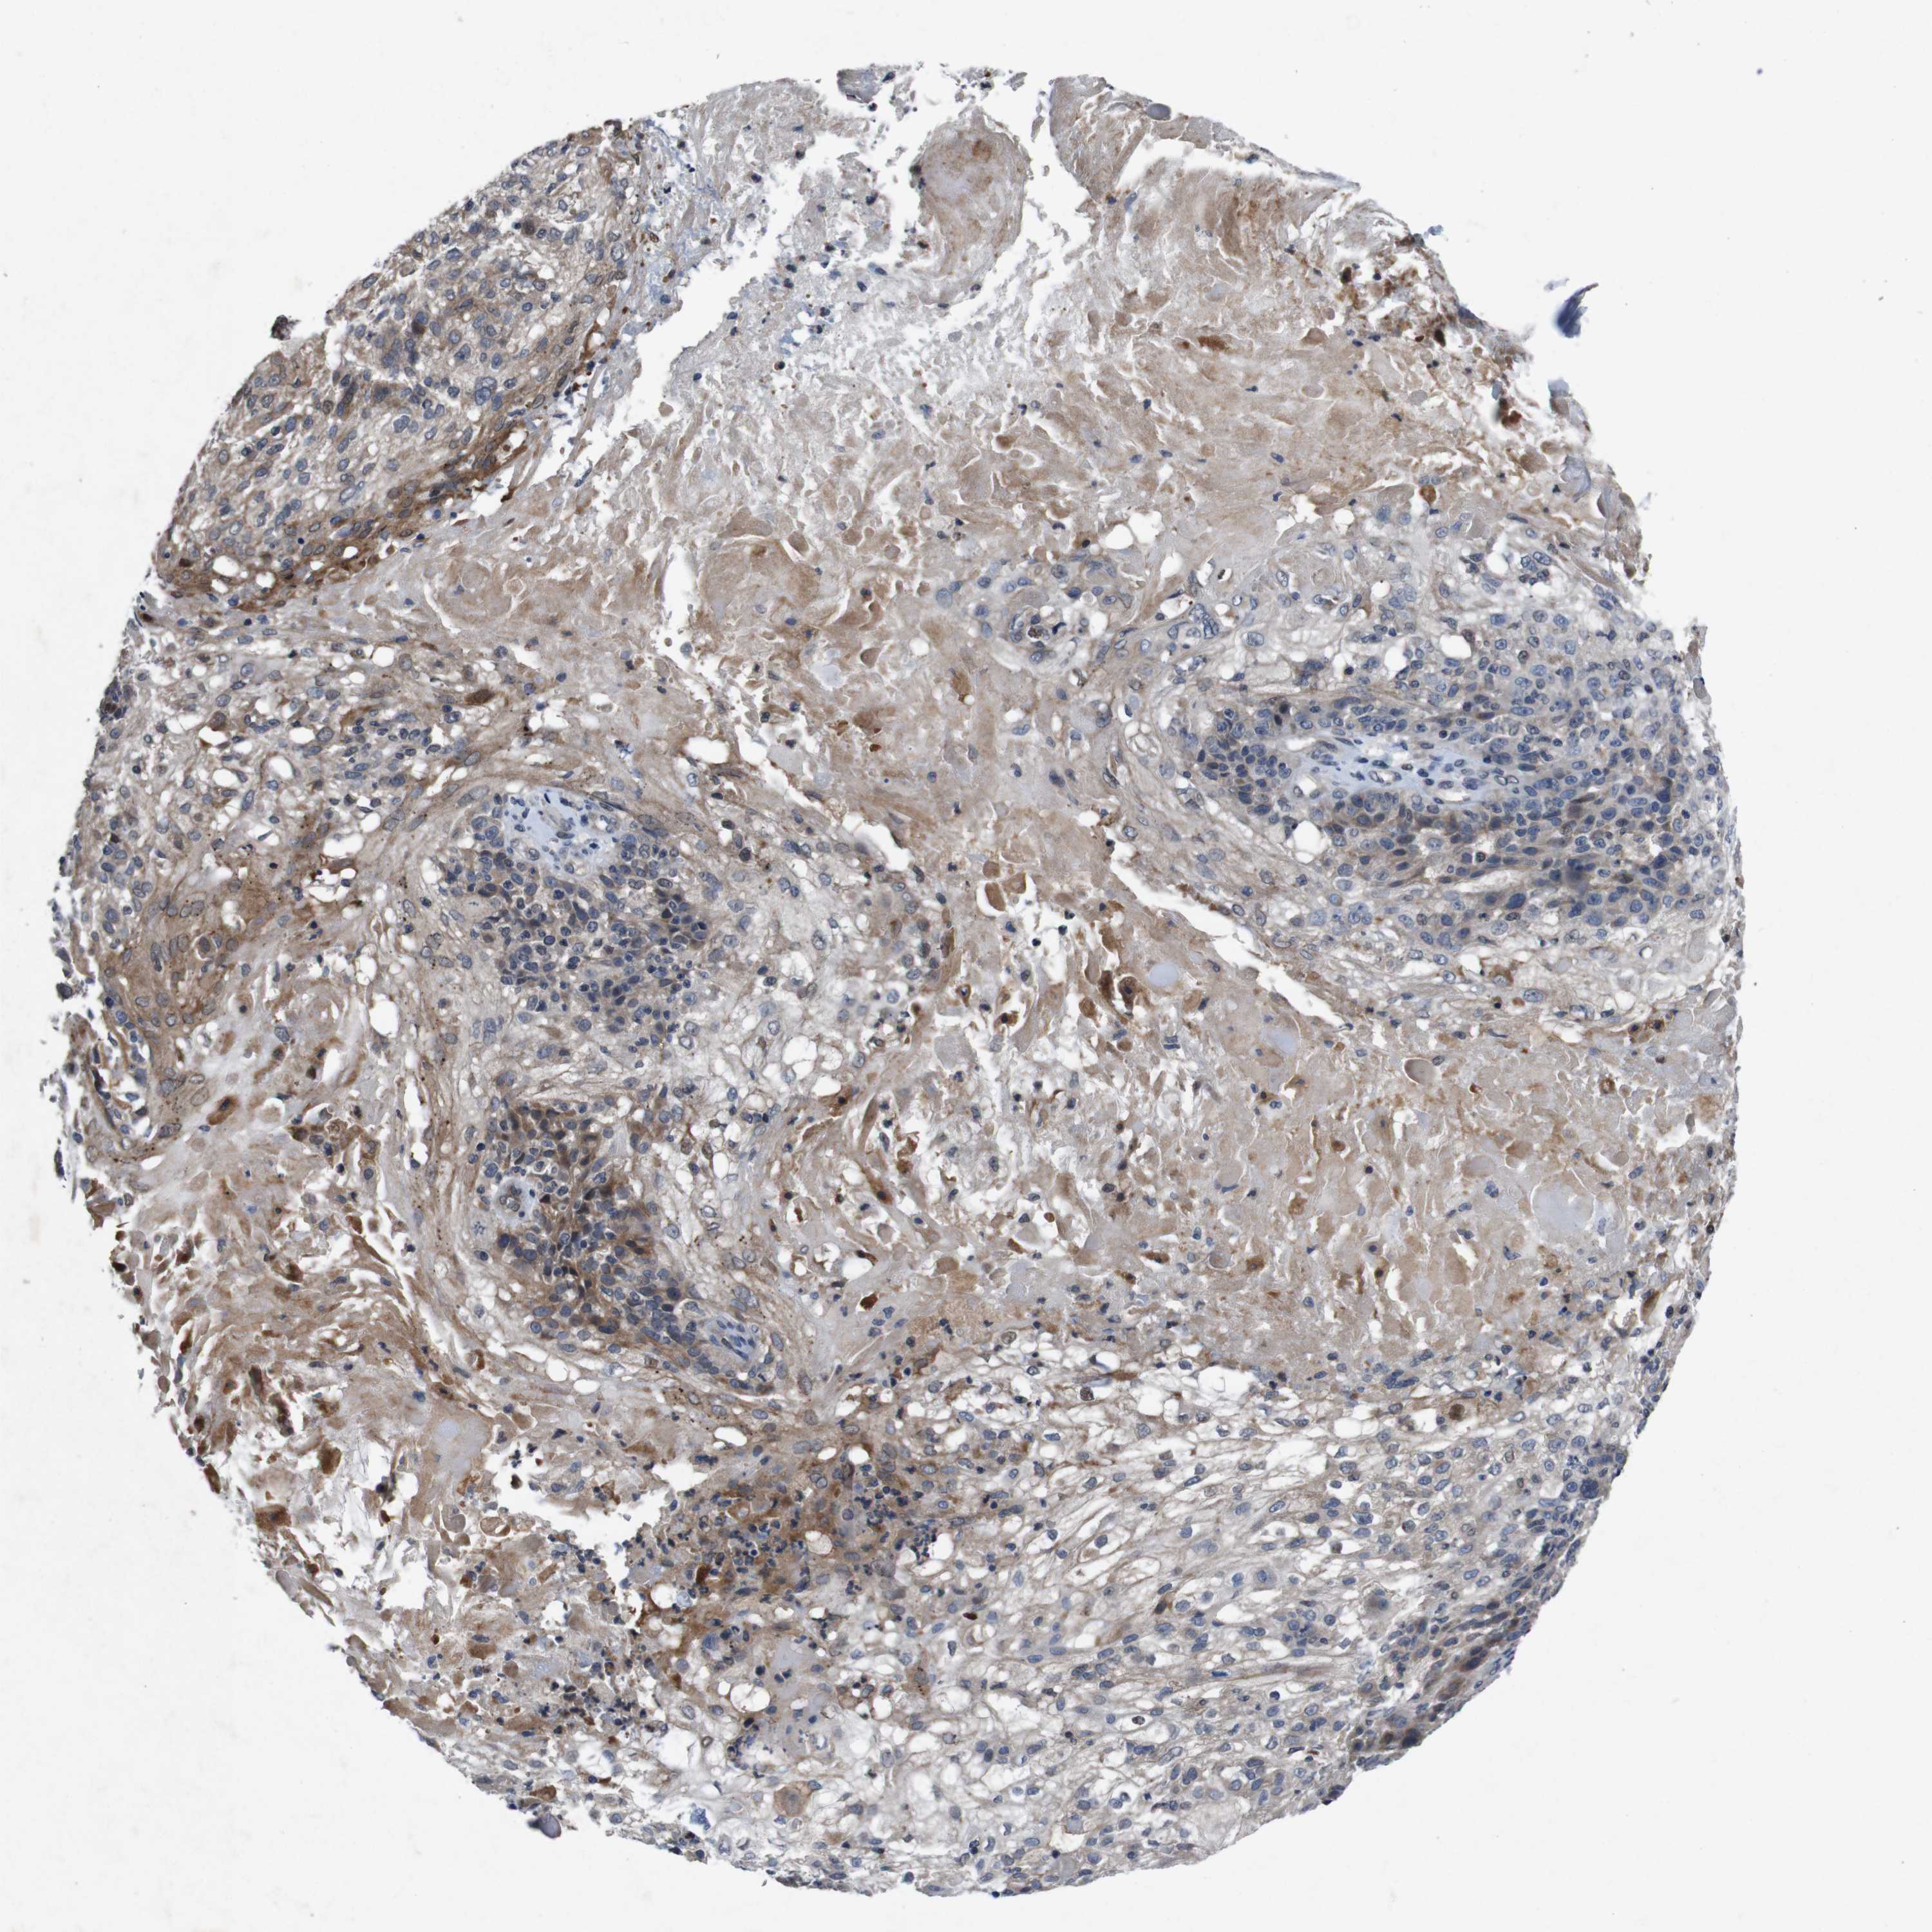

SKIN CANCER - Protein expressioni

A mouse-over function shows sample information and annotation data. Click on an image to view it in a full screen mode. Samples can be filtered based on level of antibody staining by selecting one or several of the following categories: high, medium, low and not detected. The assay and annotation is described here.

Antibody stainingi

Antibody staining in the annotated cell types in the current human tissue is reported as not detected, low, medium, or high, based on conventional immunohistochemistry profiling in selected tissues. This score is based on the combination of the staining intensity and fraction of stained cells.

Each image is clickable and will lead to virtual microscopy that enables deeper exploration of all samples and also displays staining intensity scores, fraction scores and subcellular localization as well as patient and tissue information for each sample.

Antibody HPA026441

Antibody CAB013090

Staining

High

Medium

Low

Not detected

Intensity

Strong

Moderate

Weak

Negative

Quantity

>75%

75%-25%

<25%

None

Location

Nuclear

Cytoplasmic/membranous

Cytoplasmic/membranous,nuclear

Squamous cell carcinoma, metastatic, NOS